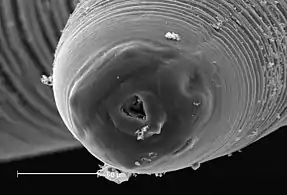

A scanning electron micrograph of the mouthparts of A. simplex

Anisakis share the common features of all nematodes: the vermiform body plan, round in cross section, and a lack of segmentation. The body cavity is reduced to a narrow pseudocoel. The mouth is located anteriorly and surrounded by projections used in feeding and sensation, with the anus slightly offset from the posterior. The squamous epithelium secretes a layered cuticle to protect the body from digestive acids.

As with all parasites with a complex life cycle involving a number of hosts, details of the morphology vary depending on the host and life cycle stage. In the stage which infects fish, Anisakis species are found in a distinctive "watch-spring coil" shape. They are roughly 2 cm long when uncoiled. When in the final host, anisakids are longer, thicker, and more sturdy, to deal with the hazardous environment of a mammalian gut.